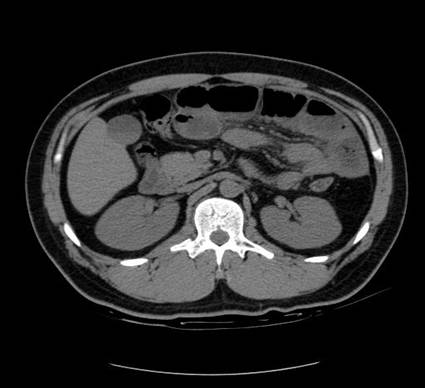

以下是引用zsl6918在2007-6-22 21:08:00的发言:[br]病史较长,反复发作,基本排除恶性病变,腹部定位像可见是小肠梗阻征象,原因无非是肠源性,血管性和神经性的,肠源性的在排除占位后应想到 肠旋转不良的可能,血管性的应想到肠系膜血管的栓塞,神经性的要想到植物神经功能紊乱的可能,本病例应该强化检查帮助诊断,个人感觉旋转不良可能性大。

以下是引用青莲居士在2007-6-24 12:27:00的发言:[br]肠梗阻[br]肝内胆管结石